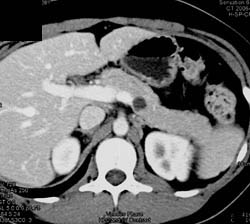

Pancreatic Pseudocyst